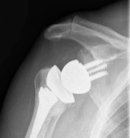

Arm lengthening after reverse shoulder arthroplasty: a review.

These authors reviewed seven articles bearing on the issue of arm lengthening after reverse total shoulder arthroplasty. They found that changes in humeral length varied from minus five to five millimetres, and changes in upper-extremity length varied from 15 mm to 27 mm. Humeral and arm shortening increased the risk of dislocation and led to poor anterior active elevation. From this literature review the authors concluded that deltoid tensioning by restoring humeral length and increasing the acromiohumeral distance is critical for adequate postoperative function and to prevent dislocation. They caution against excessive arm lengthening to avoid postoperative neurological impairment.

There is no easy answer to "how much should the arm be lengthened by a reverse total shoulder?" Some shoulders having reverse total shoulders are chronically contracted in an upward position while others are very lax. The issues of presurgical pathoanatomy, bone quality, stability, arm lengthening, neurologic injury, function, acromial fractures, and prosthesis design are interrelated and complex. As an example one of the cases in this article had a preoperative acromial fracture making it difficult to tension the deltoid; the shoulder dislocated after surgery, but this problem could not have been prevented by increasing the lengthening of the arm. Furthermore, trying to achieve stability by tensioning the deltoid with the arm at the side does not provide stability when the arm is passively abducted away from the side (a position that reduces the deltoid tension). Lateral ("East-West") tensioning of the shoulder in addition to moving the arm distally ("South" tensioning) may provide more stability throughout the range of motion and reduce the risk to the acromion and brachial plexus from a distally tight reconstruction. The change in position of the humerus relative to the scapula depends on both the prosthesis design and the placement of the glenoid and humeral components in their respective bones.

Our practice is to carefully assess and discuss with the patient the bone structure, the bone quality, the residual cuff integrity, the neurological status and the joint laxity before surgery. At surgery, we attempt to balance the soft tissues and to achieve stability by East-West as well as South tensioning, avoiding over-tensioning the deltoid to minimize the risk of nerve damage and acromial fracture. Radiographic measurements of the amount of lengthening are helpful in clinical research, as shown by this review paper.